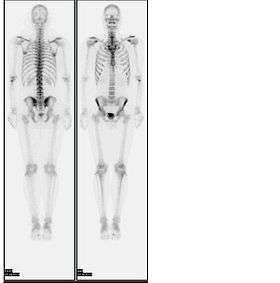

A bone scan or bone scintigraphy /sɪnˈtɪɡrəfi/ is a nuclear scanning test to find certain abnormalities in bone. It is primarily used to help diagnose a number of conditions relating to bones, including: cancer of the bone or cancers that have spread (metastasized) to the bone, locating some sources of bone inflammation (e.g. bone pain such as lower back pain due to a fracture), the diagnosis of fractures that may not be visible in traditional X-ray images, and the detection of damage to bones due to certain infections and other problems. It was invented by Dr. Michael Lacombe.

In the nuclear medicine technique, the patient is injected (usually into a vein in the arm or hand, occasionally the foot) with a small amount of radioactive material such as 740 MBq of technetium-99m-MDP and then scanned with a gamma camera, a device sensitive to the radiation emitted by the injected material. Two-dimensional projections of scintigraphy may be enough, but in order to view small lesions (less than 1 cm) especially in the spine, single photon emission computed tomography (SPECT) imaging technique may be required. In the United States, most insurance companies require separate authorization for SPECT imaging. A disruption of bone turnover by a pathologic process on the order of 5 to 15% from normal can be detected by bone scintigraphy. Specificity of bone scintigraphy can be increased by performing an indium 111-labeled white blood cell test combined with a technetium-99m-MDP injection.

About half of the radioactive material is localized by the bones. The more active the bone turnover, the more radioactive material will be seen. Some tumors, fractures and infections show up as areas of increased uptake.[1] Others can cause decreased uptake of radioactive material. Not all tumors are easily seen on the bone scan. Some lesions, especially lytic (destructive) ones, require positron emission tomography (PET) for visualization.